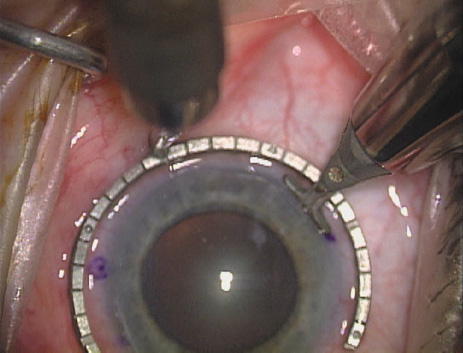

Case 1 is a 68-year-old male who presented for right cataract surgery. His refraction was −1.00 +2.25 × 80 and was recorded as reliable, consistent with his modest cataract density. Keratometry readings were 44.75 × 75 and 43.00 × 165. Corneal topography confirmed slightly more than 2.00 D of regular and slightly oblique cylinder. Consulting the nomogram, a plan was devised for a pair of LRIs to be centered over the 75-degree axis, with each incision delineating 45 degrees of arc. A single plane phaco incision was used and maintained at a size of less than 3.2 mm (Figs. 811).

Fig. 8. Steep meridian is confirmed intraoperatively by keratoscopy. In this left eye viewed from the temporal side, the “short axis” of the corneal mire is seen to be at the 75-degree meridian. (Reprinted from Hardten DR, Lindstrom RL, Davis EA. Phakic Intraocular Lenses: Principles and Practice. Thorofare, NJ: SLACK Incorporated, 2004, with permission.)

Fig. 9. The broad hash marks of the fixation ring/gauge are centered over the 75-degree meridian, using the 6:00 limbal mark for orientation. Alternatively, a Mendez gauge may be used. (Reprinted from Hardten DR, Lindstrom RL, Davis EA. Phakic Intraocular Lenses: Principles and Practice. Thorofare, NJ: SLACK Incorporated, 2004, with permission.)